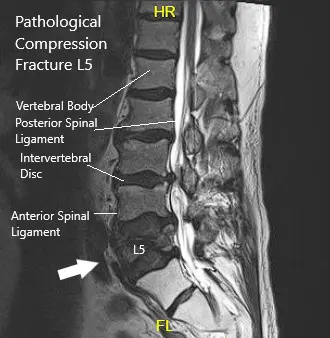

MRI showing Sagittal Section of Lumbar Sacral Spine.

MRI lumbar spine suggested acute or subacute compression fracture at L5. Degenerative changes with multilevel spinal canal or neural foraminal, subarticular recess stenosis were also present at L4-5 and L5-S1.

The patient is in remission from rectal cancer treated with surgery, radiotherapy, and chemotherapy. Imaging was done which showed a fracture of the L5 vertebra and severe stenosis at L3/4 and LS/S1 with severe neuro-foraminal disease and degenerative changes in the spine.